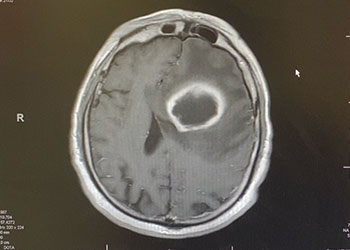

Brain:

Brain Metastasis

Author: Michael Brisman M.D., F.A.C.S., Read More!